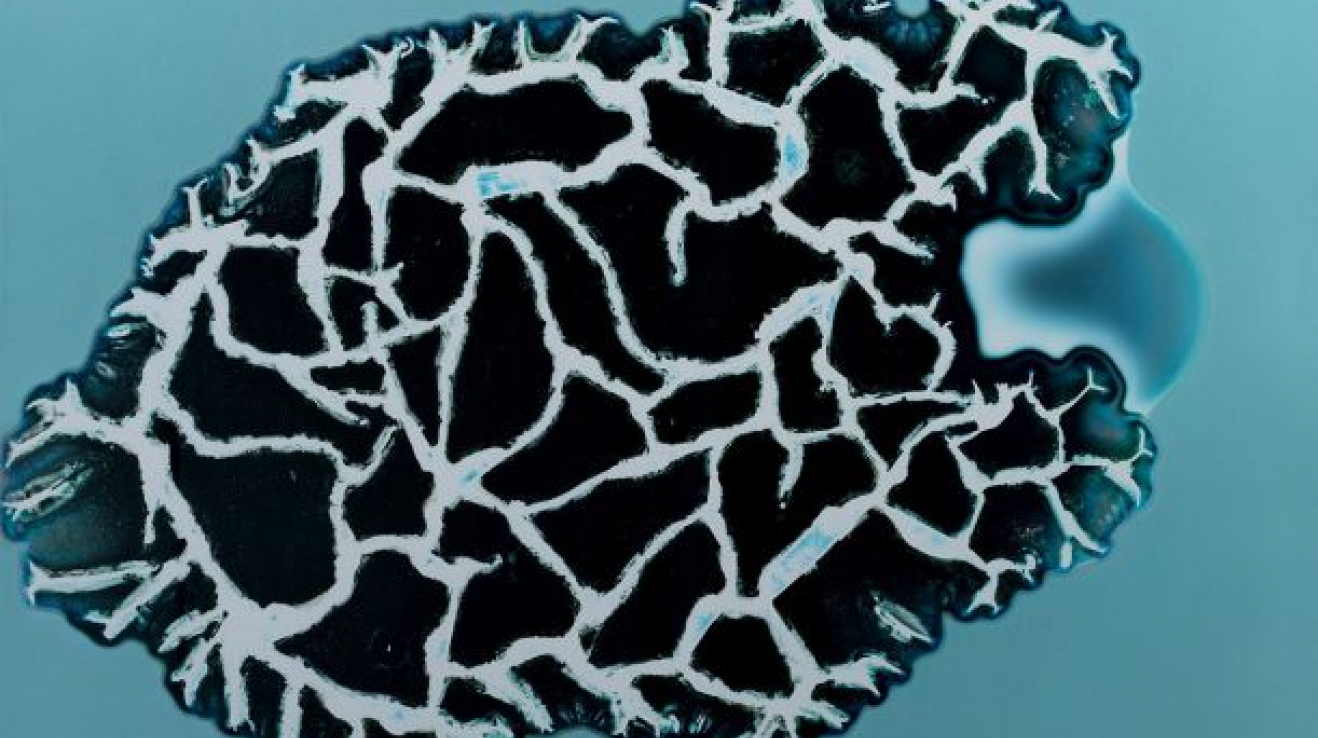

1. Valium

Valium neboli Diazepam je léčivo ze skupiny benzodiazepinů, které tlumí centrální nervovou soustavu. Používá se ke zklidnění, při úzkostech nebo třeba při léčbě epileptických záchvatů. Nabídnou vám ho před operací. Dlouhodobé užívání ale vede ke vzniku závislosti. Diazepam byl na farmaceutický trh uveden v roce 1963 firmou Hoffmann-La Roche pod výše zmíněným obchodním názvem Valium®.